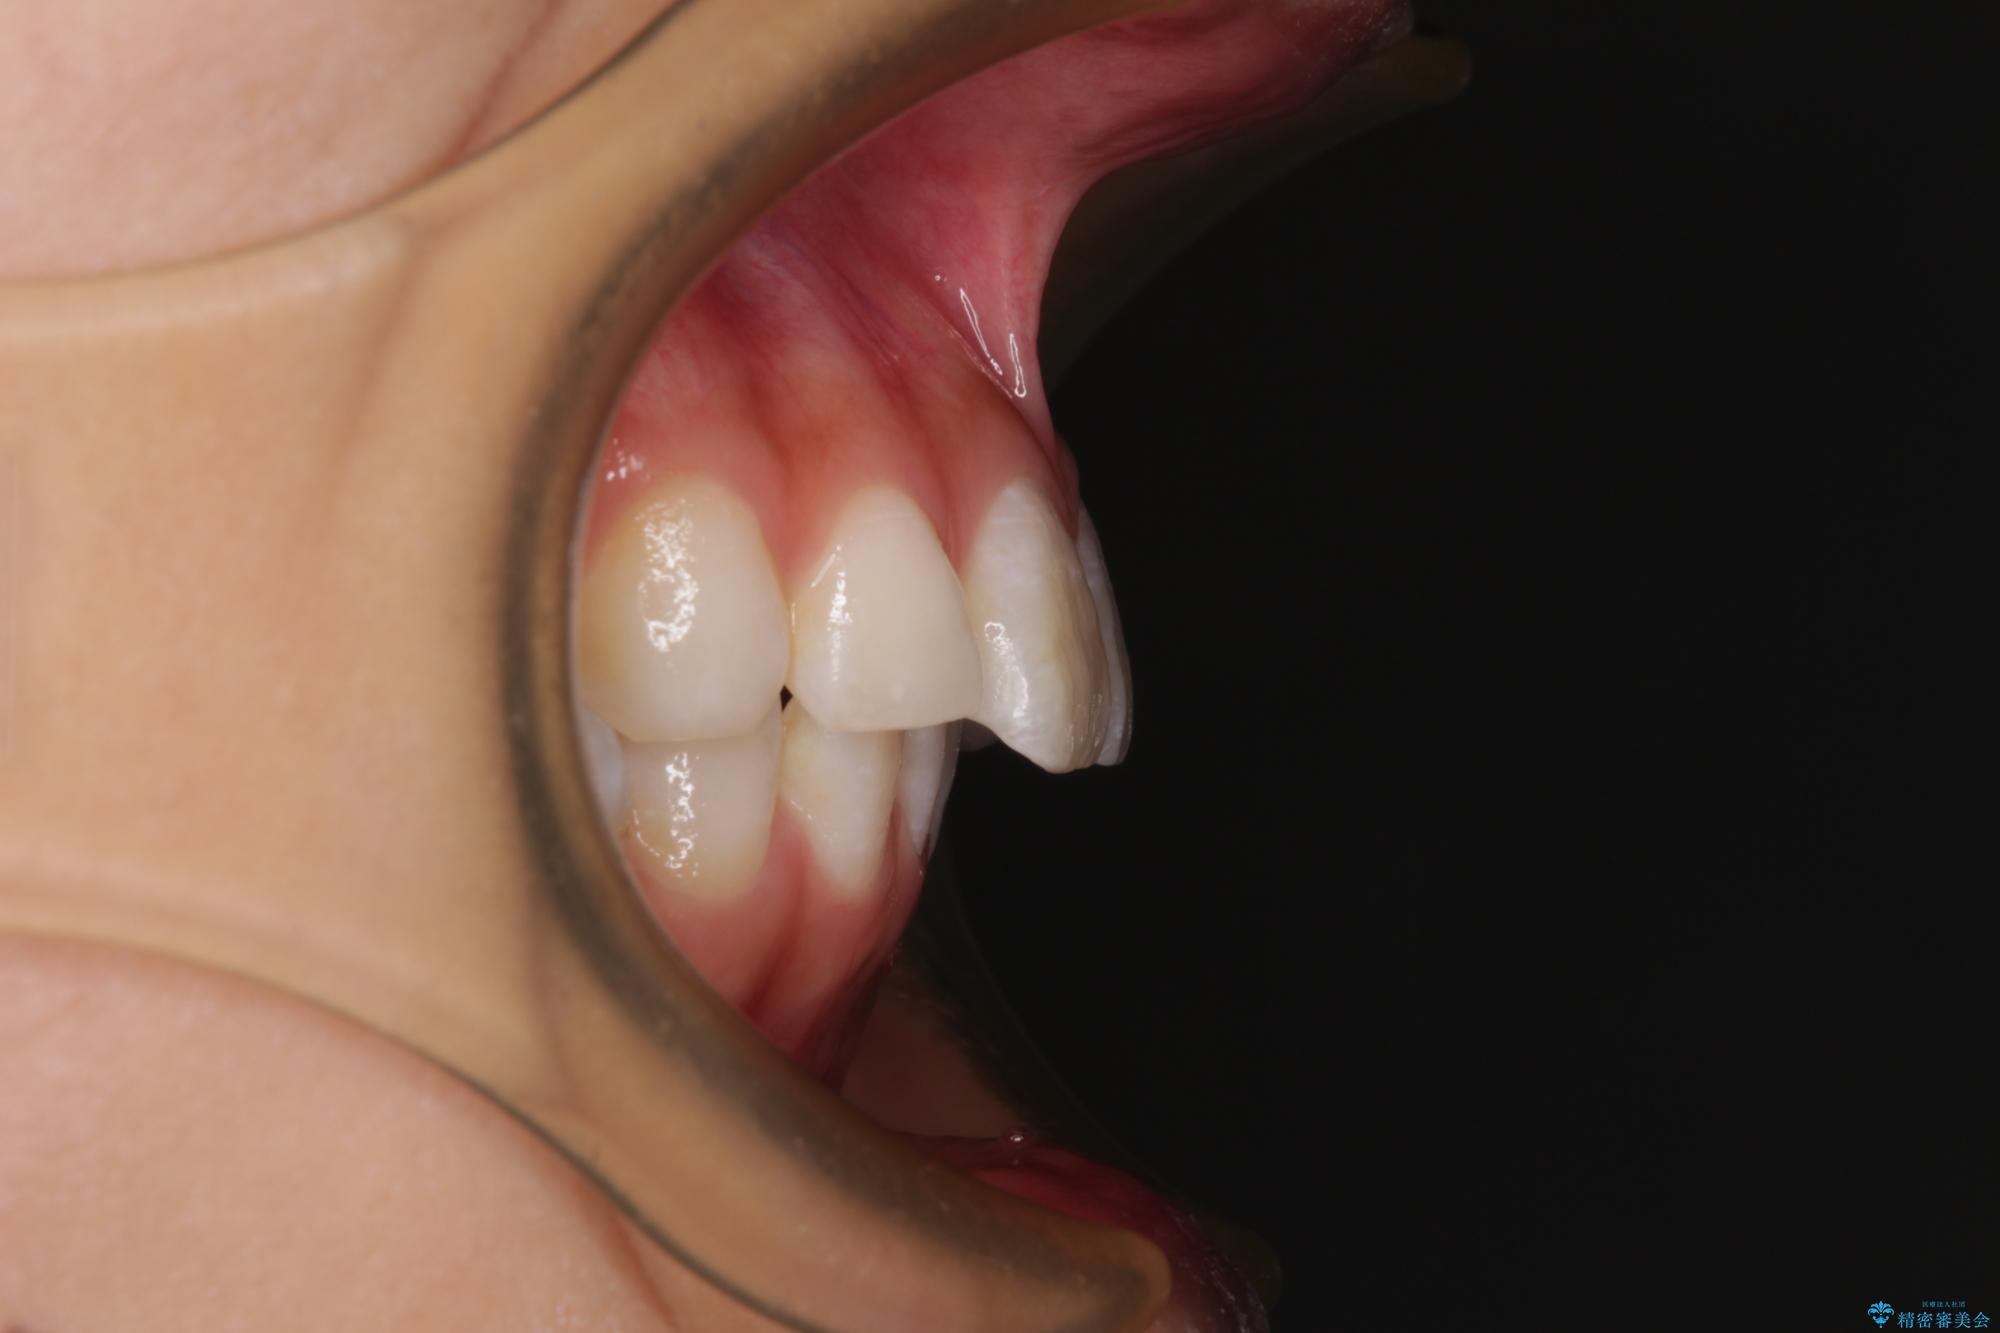

斜め前に飛び出した前歯 抜歯矯正で素敵な横顔に

- 口を閉じたときに飛び出してしまう上顎前歯を気にして来院された患者様です。

下顎はデコボコが気になっていたため、上下左右第一小臼歯4本を抜去して、ワイヤー装置にて口元の突出感を改善するよう矯正治療を行うこととしました。